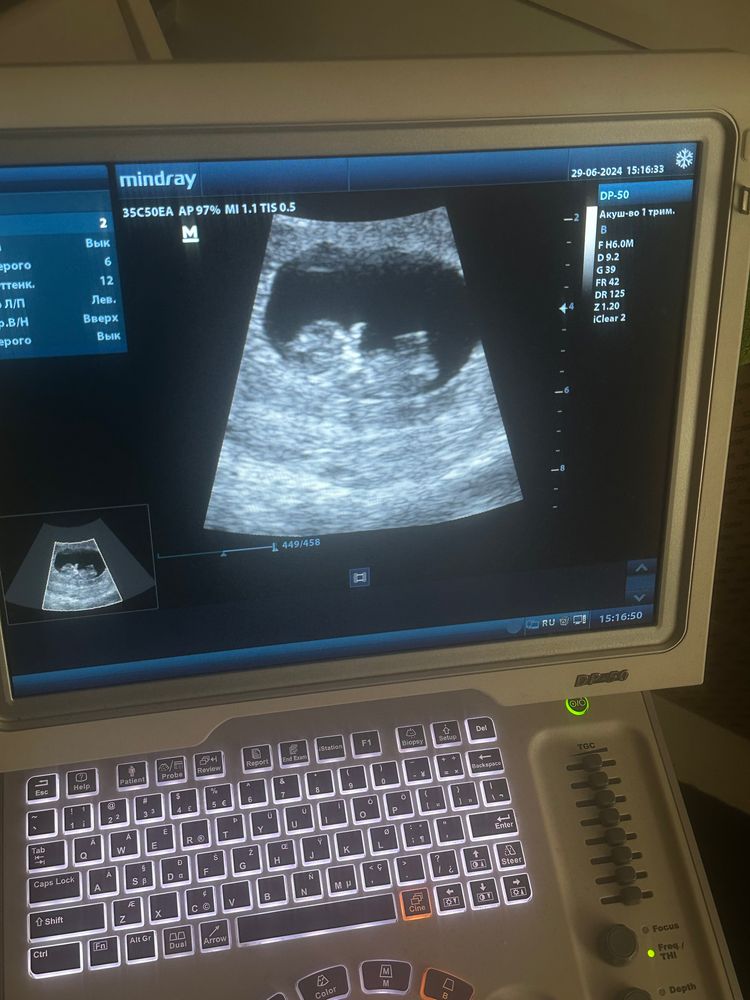

УЗИ 11 неделя